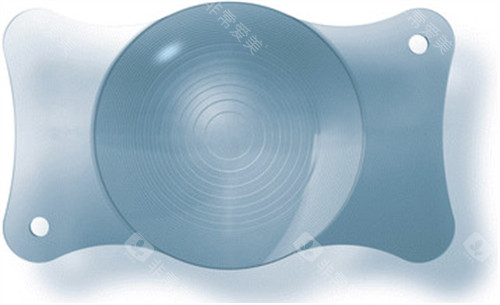

该技术通过植入具有远、中、近三个焦点的人工晶体,旨在为患者提供全程清晰的视力体验。

三焦点人工晶体置换术的核心在于,将患者原本混浊的晶状体替换为具有远、中、近三个焦点的人工晶体。

这一设计模拟了人眼的自然变焦能力,使患者在不同距离下均能获得清晰的视觉结果。

手术过程中,医生通过微小切口移除患者原有的晶状体,随后植入三焦点人工晶体,并调整其位置以确保更佳视觉结果。